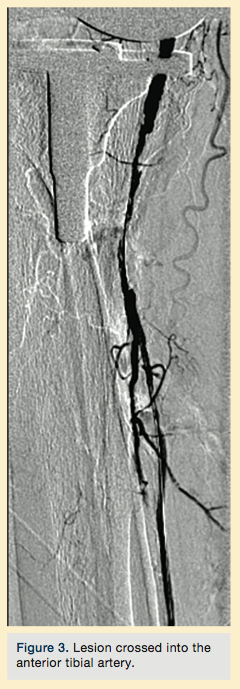

Peripheral angiography showed total occlusion of the right distal superficial femoral artery extending into the popliteal artery and into the trifurcation, with reconstitution of a peroneal and a posterior tibial. We attempted to obtain antegrade access to the lesions of the right infra-popliteal vessels (Figure 1). After failing to cross the lesion, we obtained retrograde access, puncturing from below the lesion through the posterior tibial artery near the ankle joint (Figure 2). Access was obtained and the lesion below the knee was crossed (Figure 3). Following this, the V-18 control wire (Boston Scientific) was snared from above, a CXI support catheter (CSI) was backloaded over the wire, and an antegrade Viperwire (CSI) was then placed, with removal of the retrograde sheath and wire. Atherectomy was performed with the 1.5mm Stealth 360° orbital atherectomy device (CSI) followed by balloon angioplasty with Cook, Sterling (Boston Scientific), and Chocolate (Cordis) balloon catheters. After angioplasty, significant improvement in luminal gain was noted at the expense of a dissection (Figure 4). We chose to place a Zilver PTX drug-eluting stent (Cook) within the distal superficial femoral and popliteal artery segment (Figure 5). After the procedure, the patient’s wounds completely healed. An angiogram 3 months later was performed, showing the vessels to be widely patent (Figure 6). The patient sent us a video of himself finally walking, and without pain (Video 1; online).